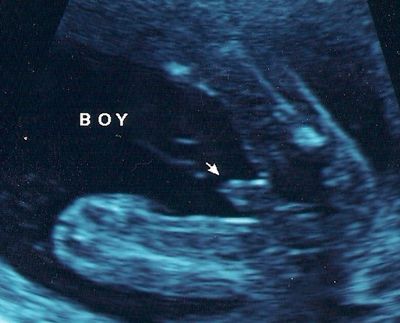

عکس جنین پسر در سونوگرافی هفته بیستم و سوم بارداری

آلت تناسلی پسر بطور واضح در بین پاهای او مشخص در هفته بیست و سوم بارداری می باشد. در هفته بیست و سوم شما 5 ماهه باردار هستید. جنین شما حدود 501 گرم وزن دارد و قدش 28.9 سانتی متر است. او حالا به اندازه یک گریپ فروت است.